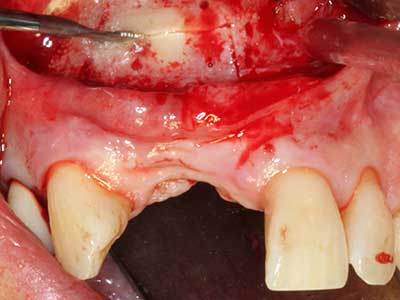

En la extracción de bloques óseos la piezocirugía también presenta ventajas adicionales: Además de la alta precisión en la osteotomía que ya se ha descrito antes, se ha comprobado que el uso de los delgados insertos de sierra resulta especialmente cuidadosas con el hueso. Frente a esto, sobre todo cuando se usan las fresas de Lindemann, cabe esperar pérdidas en la extracción significativamente más altas debido al mayor grosor de la parte frontal del cabezal (Lakshmiganthan, Gokulanathan et al. 2012). La separación basal que se necesita en particular en los injertos de bloque extraídos de forma retromolar se ve facilitada mediante sierras perpendiculares especialmente previstas a tal fin, lo que permite considerar que la cirugía piezoeléctrica es un procedimiento preciso y seguro para la obtención de bloques de hueso en el área retromolar (Happe 2007) (fig. 1-12).

Fig. 1: Preparación de una tapa ósea conforme con Piezomed (W&H, Salzburgo, Austria)

Fig. 2: Defecto del maxilar superior lateral vertical y horizontal con línea de la sonrisa alta, con indicación para la reconstrucción antes del implante.

Fig. 3: La separación basal del bloque se ve facilitada con piezas dotadas de una angulación especial.

Fig. 4: Con la rasqueta ósea se obtienen virutas adicionales de hueso autógeno.

Fig. 5: Comprobación de las dimensiones del bloque en la zona de recepción.